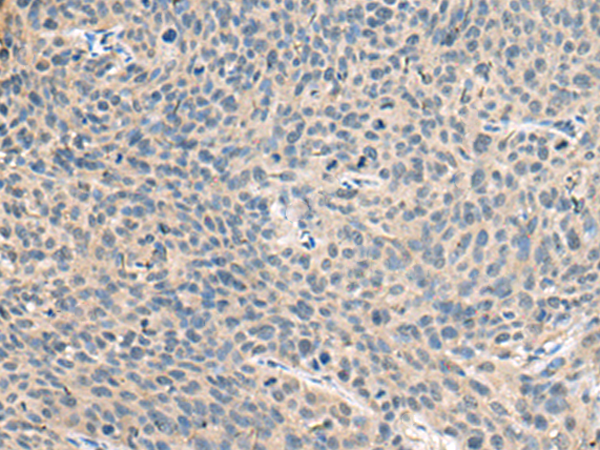

IHC positive control:

Human cervical cancer

IHC Recommend dilution:

50-100